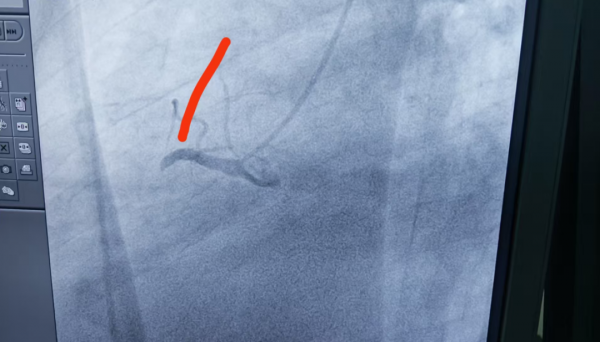

2、71歲男性,右冠閉塞,行藥物球囊擴張成形術。